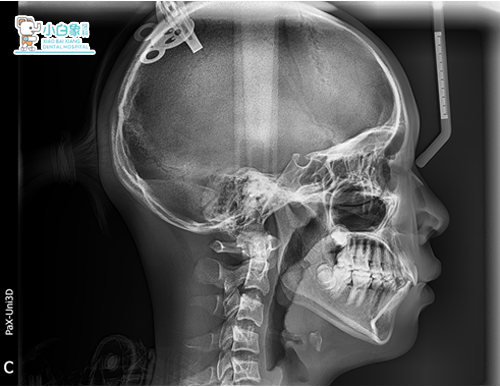

患者:***    女     13岁

主诉:牙不齐,求治。

现病史:患者换牙后发现牙列不齐,影响美观,来诊。

双颌稍前突 治疗前

治疗前

安氏一类错合

深覆合 深覆盖二度

牙列拥挤